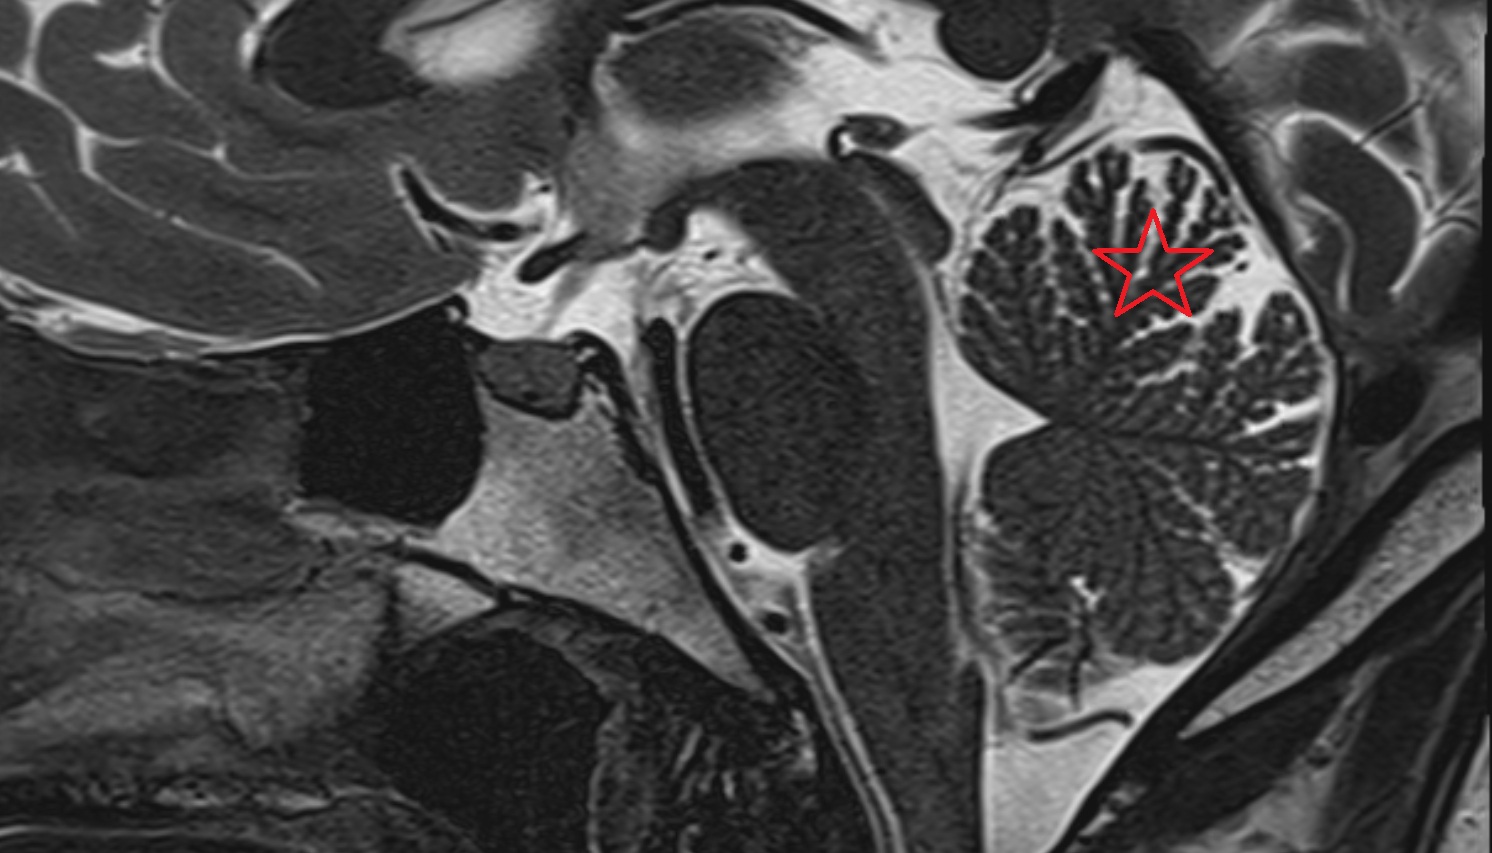

- Paramedian lobule (HVII) of cerebellum

- Simple lobule (HVI) of cerebellum

- Anterior quadrangular lobule (HV) of cerebellum

- Anterior quadrangular lobule (HlV) of cerebellum

- Biventral lobule (HVIII) of cerebellum

- White matter of cerebellum (Arbor vitae)

- Cerebellar tonsil (H IX)